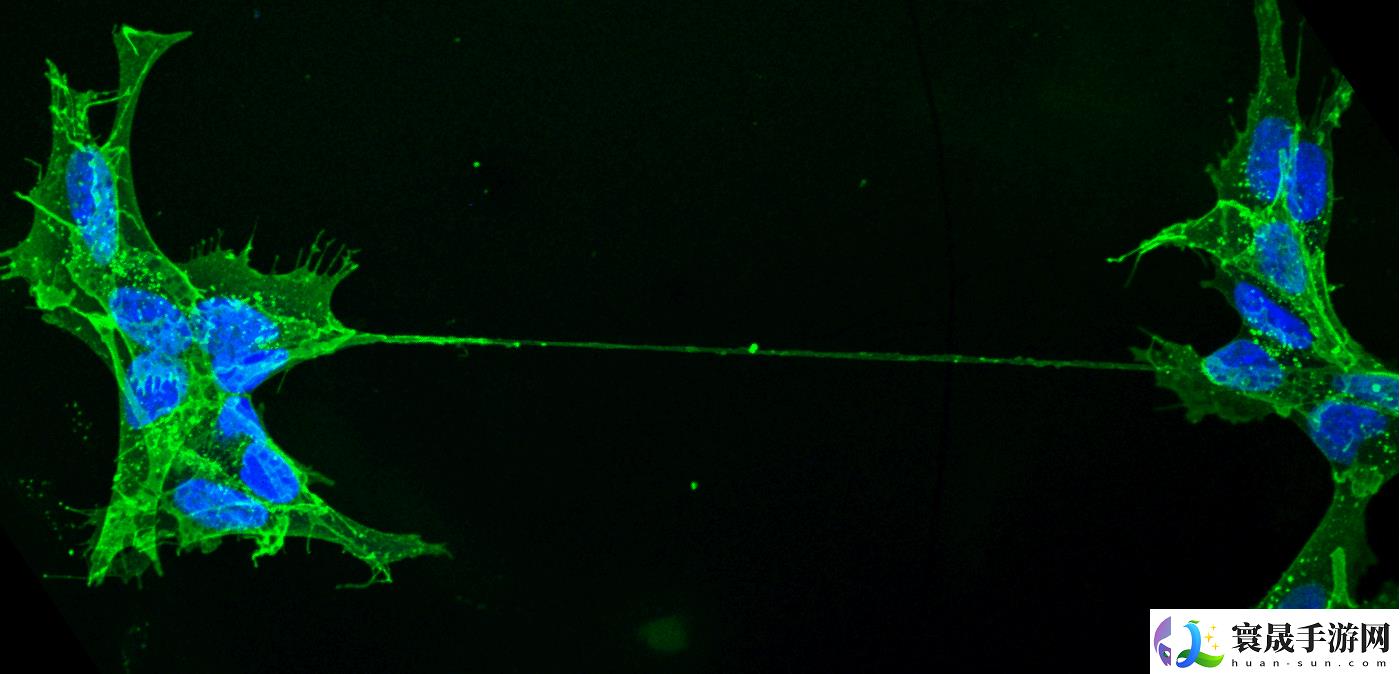

自 2003 年德国与瑞士团队首次在体外实验中观察到 TNT 以来,科学界对这一结构的生物学意义长期存在争议。为突破研究瓶颈,巴斯德研究所膜运输与发病机制单元负责人 Chiara Zurzolo 教授率领由 15 名青年科学家组成的国际团队,选用具有透明特性的斑马鱼胚胎作为研究对象,通过荧光标记技术与活体显微成像技术(包括 3D 活细胞荧光显微镜、超分辨率显微镜及冷冻电镜),首次捕捉到活体生物中 TNT 的动态形成过程。

研究发现,斑马鱼胚胎细胞间延伸出的细长中空管状结构确认为 TNT,并观察到线粒体通过该通道在细胞间转移的现象。“这不仅证实 TNT 在活体内的存在,更表明其对胚胎健康发育具有重要作用。”Zurzolo 强调。此前,科学界仅在体外实验中观察到此类现象。